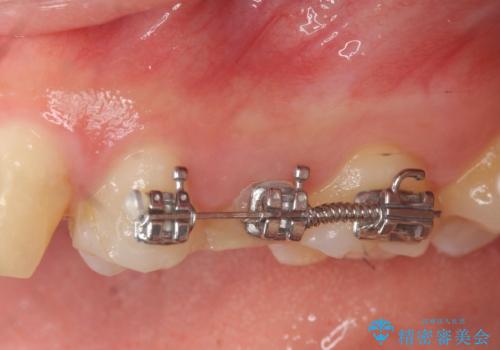

挺出小矯正を行った縁下カリエス治療

X線撮影を行い、隣接面に多発した虫歯と歯ぐきよりも深くなってしまった虫歯を小矯正をおこなったのちのセラミック治療で問題を解決します。

小矯正を行い深い虫歯を改善した後は、小手術を行うことで歯ぐき・周囲歯槽骨の状態を整えることでより安定した歯周環境を得ることができます。